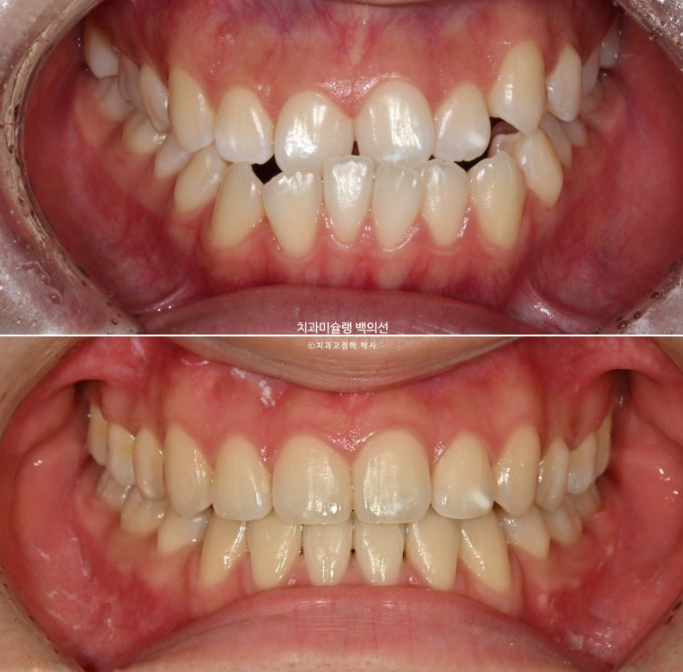

약 2년전, 교정치료를 위해 내원한 환자분입니다.

위아래 중심선이 서로 약 2mm가량 어긋나 있고 송곳니 덧니도 있습니다.

주걱턱으로 인해 앞니가 거꾸로 물립니다.

반대교합이라고 합니다.

이제 전후 비교 보겠습니다.

23.11~25.10

어긋나 있던 위아래 중심선이 일치되었습니다.

앞니가 거꾸로 물리는 반대교합이 해결되었습니다.